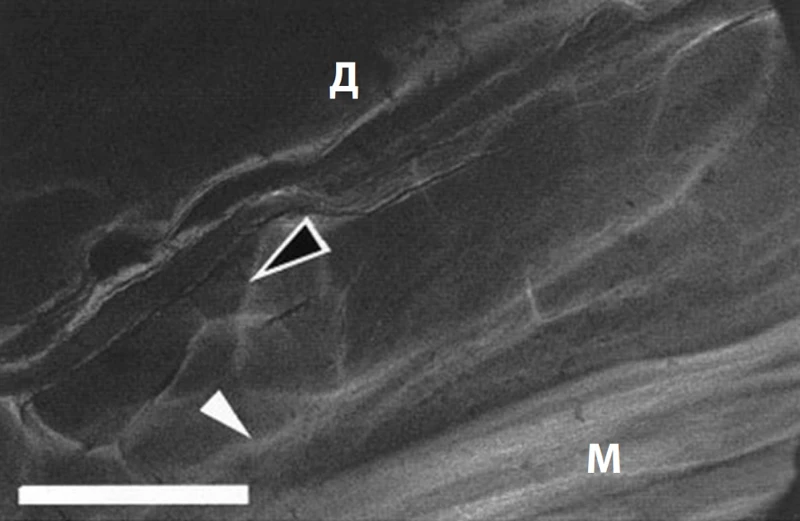

• жировой слой и дерма (образуют фибросептальную сеть, которая разделяет жировую ткань на дольки и затем крепится к дерме, формируя связки кожи retinaculum cutis; RC). RC защищают кожу от гравитации и растяжения, а также сохраняют трехмерную волокнистую структуру (рис. 2)3. С возрастом происходит уменьшение площади и толщины RC, параллельно усугубляется дряблость кожи (рис. 3, 4)4, 5.

Рис. 2. Кожные связки (retinaculum cutis; RC) / фибросептальная сеть жировой ткани (ФСС) передней поверхности предплечья. Белые стрелки – глубокая фасция, черные – RC. М – мышца; Д – дерма3.